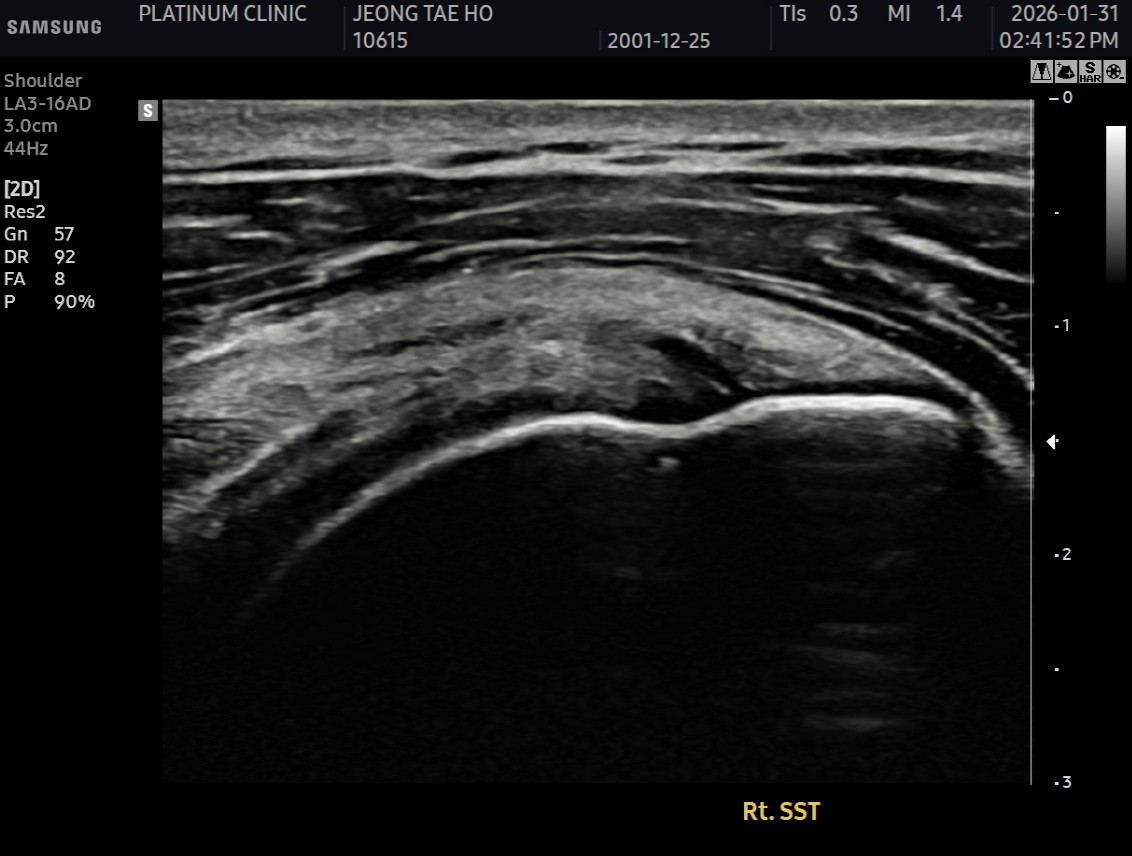

초음파와 MRI 검사 결과, 환자분은 회전근개 극상건의 점액낭면 부분파열 상태였습니다. 파열 크기는 약 1cm, 근육 위축이나 지방 변성은 심하지 않았습니다.

초음파 검사 결과, 이전에 검게 보이던 파열 부위가 정상 인대처럼 하얗게 재생되어 있었습니다.